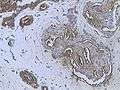

Invasive ductal carcinoma of the Breast assayed with anti Mucin 1 antibody.

Invasive ductal carcinoma of the Breast assayed with anti Mucin 1 antibody..jpg) Breast cancer (Infiltrating ductal carcinoma of the breast) assayed with anti HER-2 (ErbB2) antibody.

Breast cancer (Infiltrating ductal carcinoma of the breast) assayed with anti HER-2 (ErbB2) antibody..jpg) Histopathology of invasive ductal carcinoma of the breast representing a scirrhous growth. Core needle biopsy. Hematoxylin and eosin stain.

Histopathology of invasive ductal carcinoma of the breast representing a scirrhous growth. Core needle biopsy. Hematoxylin and eosin stain. Invasive ductal carcinoma of the breast. H&E stain.

Invasive ductal carcinoma of the breast. H&E stain.- Histopathology of invasive ductal carcinoma of the breast representing a scirrhous growth. Core needle biopsy. HER-2/neu oncoprotein expression by Ventana immunostaining system.

Histopathology of invasive ductal carcinoma of the breast. H&E stain.

Histopathology of invasive ductal carcinoma of the breast. H&E stain.